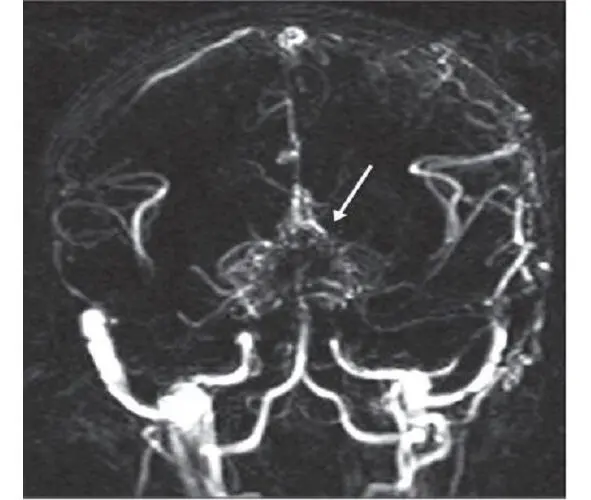

Moyamoya is a rare disease [208] characterized by a progressive spontaneous stenosis or occlusion of a supraclinoid segment of an ICA (single or both) at the level of the siphon and the initial segments of the anterior cerebral artery (ACA) and the middle cerebral artery (MCA) with the subsequent involvement of the VBS. The specific feature of this disease is the secondary formation of a basilar, anastomotic capillary network, resembling a small cloud of smoke (Fig. 4) during the angiographic imaging, which is pronounced in Japanese as «moyamoya». This word has become an official name of the disease. In 40% of cases in the moyamoya disease a bilateral impairment of the ICA is noted; initially the ICA is involved only on one side [233; 285]. The «moyamoya syndrome» term is more often used for angiographic description of the pathology [266].

Fig. 4:MRA of a patient with the moyamoya disease. The secondary formation of anastomotic network resembling a cloud of smoke is indicated with an arrow.